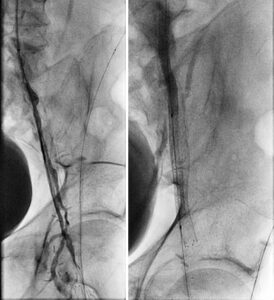

Figure 4. Follow-up angiogram at 40 months (new stent shown with white arrows; occluded stent with black arrows)

Angiography performed 3 years and 8 months following the procedure demonstrated excellent patency of the DBS (Picture). Interventions were performed at sites other than the double-barrel stent.

A Sept. 2016 US follow-up showed continued patency. The patient had no clinical symptoms of claudication.